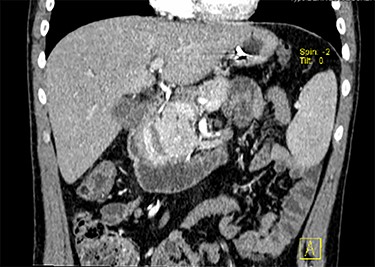

Blood tests showed no anaemia nor leukocytosis but transaminases and C-reactive protein were slightly elevated. He had an abdominal and thoracic computerized tomography scan (CT) done in the ED that revealed a large duodenal tumour, approximately 6 cm diameter, with an associated intramural haematoma and one enlarged lymph node in the liver pedicle, 19 × 13 mm (Figs 1 and 2). There was no distant metastasis. Additionally, he underwent an upper digestive endoscopy in the ED, confirming the presence of an extensive, nodular, polypoid and obstructive duodenal tumour in its first and second portions, including the major papilla. However, biopsies turned out to be inconclusive. Later, he also had a magnetic resonance done that ruled out invasion of adjacent structures, except for the pancreatic head. Finally, he underwent an endoscopic ultrasound (EUS) with biopsies showing a duodenal NET, with diffuse expression of CK7, chromogranin and synaptophysin, and Ki-67 expressed in less than 2% of the cells.

CT scan with contrast, coronal view of the large duodenal mass. Note the polypoid solid mass, in the medial border of the second portion of the duodenum, of approximately 6 cm, enhanced by contrast, slightly heterogeneous and invading the pancreatic head parenchyma. More proximally, in the right lateral border of the first portion of the duodenum, there is an extramural haematoma, well-defined, of approximately 4 × 2 cm, non-enhanced by contrast. Note also a slight dilation of the intrahepatic biliary ducts, and the main bile duct, with a progressive distal narrowing, resulting from compression of the duodenal mass.